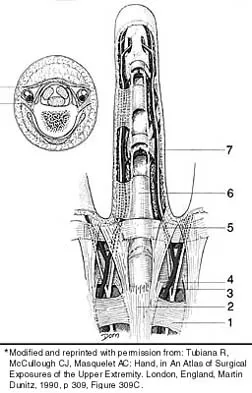

Which of the following anatomic structures is labeled 6 in Figure 27?

Explanation